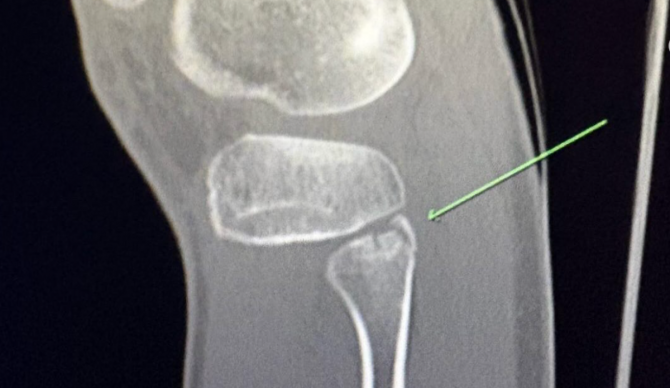

“In my Round of 32 heat at Pipe on my second-to-last wave, I got compressed into my board, as I was trying to squeeze out the end of a barrel,” Callinan wrote. “I felt something pop in my knee, but didn’t think it was too serious. Flew home the following day for a quick turnaround to Abu Dhabi, nursing my warm-up waves, seeing how it faired. I pushed through not knowing until I got home the severity of what I had done. I ended up fracturing the head of my fibula, which is a bizarre place, but minimal other damage.”